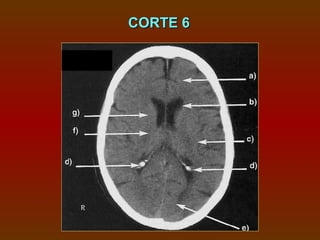

CORTE 6

a) Lobo frontal

b) Corno frontal do ventrículo lateral

c) Lobo parietal

d) Plexo coróide (calcificado)

e) Lobo occipital

f) Cápsula interna

g) Núcleo caudado

CORTE 6 a) Lobofrontal b) Corno frontal do ventrículo lateral c) Lobo parietal d) Plexo coróide (calcificado) e) Lobo occipital f) Cápsula interna g) Núcleo caudado